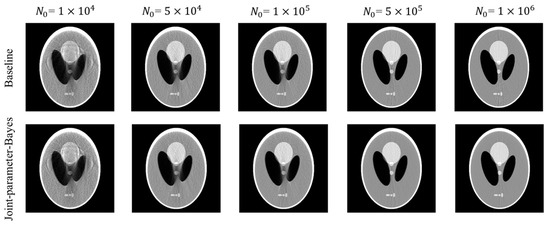

3.1.1. Reconstruction Comparison

3.1.2. Stopping Criterion Investigation

| Incident Flux | RMSE | SSIM | PSNR | Iterations | RMSE | SSIM | PSNR | Iterations |

| 0.0065 | 0.9744 | 43.69 | 1000 * trial number | 0.0067 | 0.9731 | 43.53 | 1000 | |

| 0.0048 | 0.9864 | 46.36 | 1000 * trial number | 0.0051 | 0.9853 | 45.83 | 1000 | |

| 0.0042 | 0.9898 | 47.46 | 1000 * trial number | 0.0046 | 0.9885 | 46.73 | 1000 | |

| 0.0033 | 0.9941 | 49.68 | 1000 * trial number | 0.0038 | 0.9931 | 48.25 | 1000 | |

| 0.0031 | 0.9946 | 50.04 | 1000 * trial number | 0.0037 | 0.9937 | 48.53 | 1000 | |